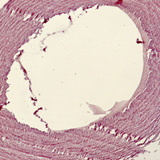

从一个鸽子的主动脉到平滑肌细胞和内皮细胞

放大50倍